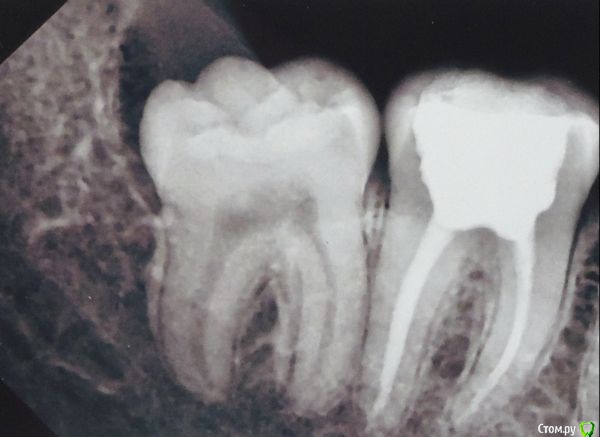

София С Опубликовано 24 ноября, 2017 Автор Поделиться Опубликовано 24 ноября, 2017 (изменено) Большое спасибо за ответы.Есть ещё вопрос:- 38 был удалён вследствие воспаления, нагноения, возникшего под капюшёном, и распространившемся далее, в неблагоприятное время в неблагоприятном месте ( учёба в далёкой азиатской стране ). Там, во время визитов к стоматологу, делались промывки, удаление было отложено к возвращению домой...Теперь 48 - так же закрыт капюшёном, вот снимки. Может, достаточно иссечь его и всё? Визит к хирургу ещё только планируется, снимок 48 сделан заблаговременно, одновременно с 37 Изменено 24 ноября, 2017 пользователем София С Ссылка на комментарий

red_butler Опубликовано 24 ноября, 2017 Поделиться Опубликовано 24 ноября, 2017 4.8 удалять Ссылка на комментарий

igorstom Опубликовано 24 ноября, 2017 Поделиться Опубликовано 24 ноября, 2017 Может, достаточно иссечь его и всё? Визит к хирургу ещё только планируется, снимок 48 сделан заблаговременно, одновременно с 37Когда дело касается: удалять или решить проблему иссечением, то предыдущий опыт должен подсказать решение: если удаление было сложным, а процесс заживления и болезненности достаточно не быстрым, на мой взгляд лучше иссечь. Другой разговор, если Вы будете в недалеком будущем заниматься ортодонтией (то есть исправлять положение зубного ряда), в этом случае лучше заблаговременно удалить восьмой зуб. То что мы часто советуем пациентам не значит, что точно также поступаем со своими зубами. Был у меня случай, когда у меня лечился мой близкий товарищ и коллега стоматолог-ортопед. С руками у него всё порядке. И когда я возразил ему, мол, ну ты же сам ортопед и знаешь, что в твоем случае показана вкладка и коронка, он чуть ли не со слезами: "Игорь, я не хочу коронку!". 1 Ссылка на комментарий

igorstom Опубликовано 24 ноября, 2017 Поделиться Опубликовано 24 ноября, 2017 Каналы на последнем рентгеновском снимке вылечены, если судить рентгенологически очень неплохо. А вот пломбы оставляют желать лучшего. Хотя опять же, по снимку, в силу огромной пломбы явные показания к протезированию. Ссылка на комментарий

igorstom Опубликовано 25 ноября, 2017 Поделиться Опубликовано 25 ноября, 2017 Ну тогда лучше удалить. "С глаз долой, из сердца вон". Всё равно, рано или поздно придется от него избавиться. Почему? Изначально непрорезавшиеся полностью или кривовато, восьмые сложнее поддаются адекватной гигиене и самоочищаемости. И соответственно быстрее разрушаются. И часто способствуют разрушению стенки соседнего 7-го зуба, с краями которого соприкасаются. Ссылка на комментарий